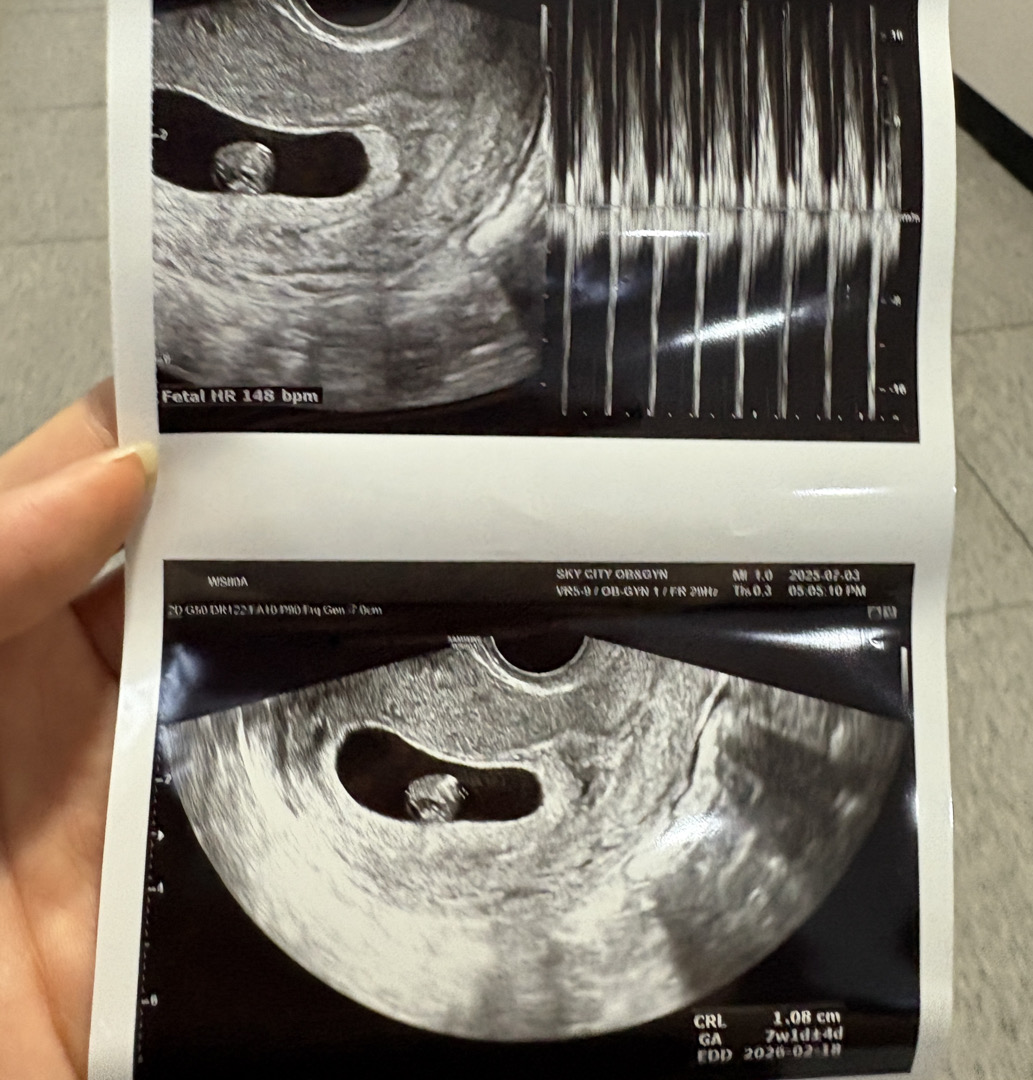

7주차 초음파 모양한번 봐주세요ㅠㅠ

7주차인데 심장소리는 잘들렸어요 근데 의사쌤이 애기 모양이 좀 이상한거같다고 일단 지켜보자하는데 ㅜㅜ 문제있는걸까요??ㅜㅜ7주차면 다들 어떤 모양들일가요..?